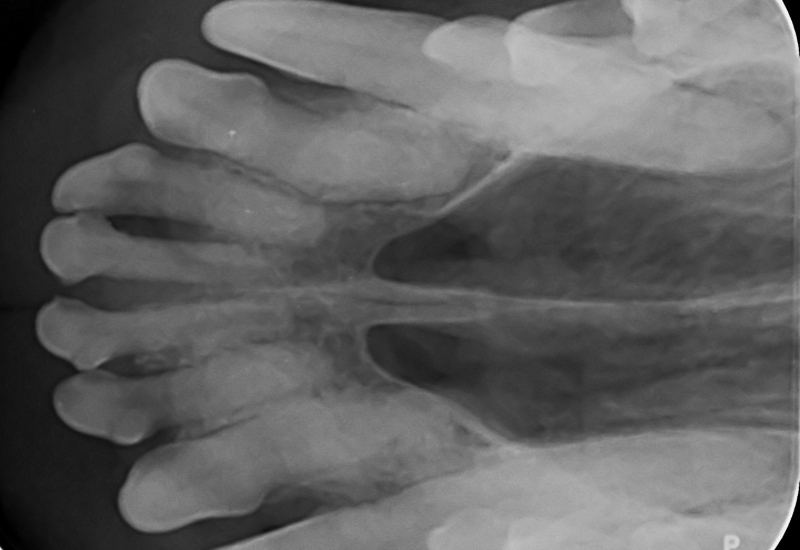

We beschikken over moderne gebitsapparatuur, waardoor we bijna alle gebitsbehandelingen in huis kunnen verrichten.